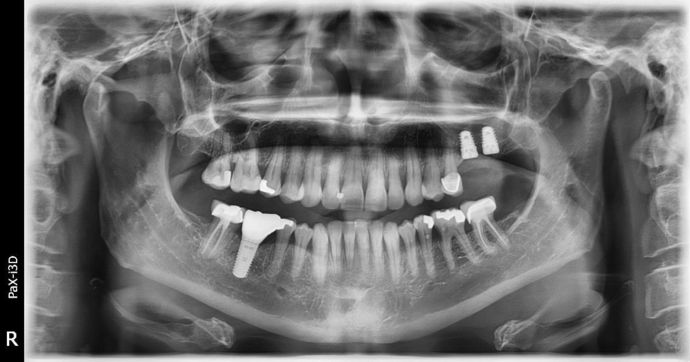

Dental Implants: Case 3 - Freeport

2 implants were placed on the upper left side, we had very little bone to work with. A 6 mm sinus augmentation was needed on the back implant and a 4 mm augmentation was needed on the more forward one. We did all of that at the time of implant placement here at the office. We finished the case using a fixed bridge to more evenly spread the load, we have a ton of bone that can be seen around the implants and it is still calcifying/healing towards the tops of the implants! I love complicated surgical cases like this, there is such a sense of accomplishment! I'll just borrow a saying here: WINNING!